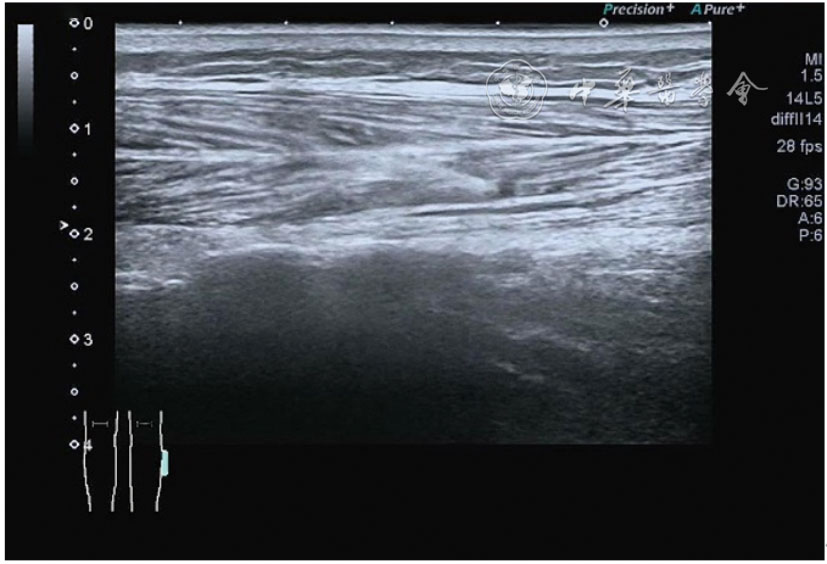

髂胫束的最佳显示切面为长轴切面,采用高频探头,扫查深度<3 cm。超声表现胫骨附着点处骨皮质不规则,髂胫束增厚,回声减低,其周围组织水肿,血流增加(图26)。股骨髁部肿胀、增厚,回声减低,超声触诊可能诱发股骨外侧髁处的疼痛。部分患者可见髂胫束滑囊扩张,内为无回声积液(图27)。

图26 超声图像显示胫骨附着点处骨皮质不规则,髂胫束增厚,回声减低,其周围组织水肿,血流增加

图27 超声图像显示股骨髁部肿胀、增厚,回声减低,部分患者可见髂胫束滑囊扩张